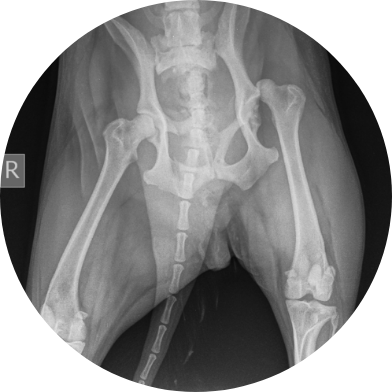

슬개골탈구,고관절질환,십자인대,척추디스크,골관절염

고관절 질환은 통증과 보행 이상을 일으키는

흔한 관절 문제로 조기 진단과 치료가 아이의

건강한 움직임을 지키는 데 중요합니다.